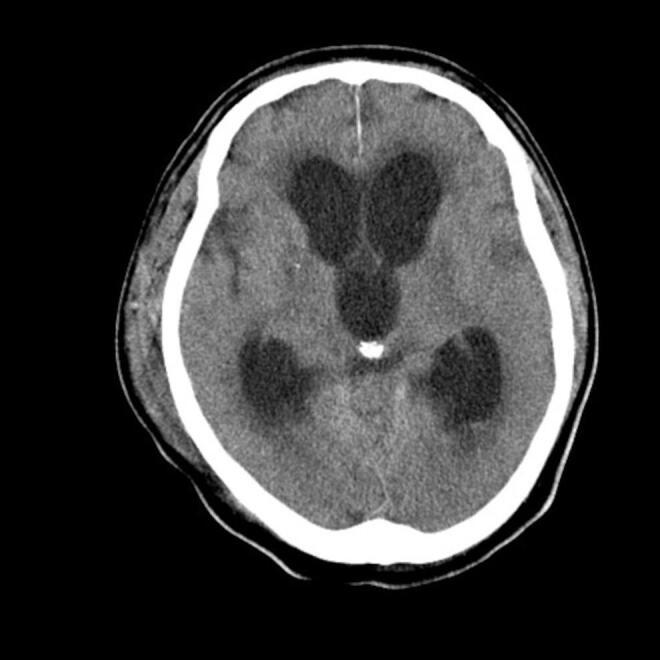

Meningitis-related acute hydrocephalus is rare, challenging to diagnose, and has a high mortality rate.

Here we describe the case of a 76-year-old patient diagnosed with bacterial meningitis who developed acute hydrocephalus and subsequently died.

Although meningitis-related acute hydrocephalus is usually non-occlusive, occlusive hydrocephalus may also occur. Moreover, worsening hydrocephalus despite cerebrospinal fluid drainage should prompt a diagnosis of obstructive hydrocephalus. In such conditions, potential management strategies include ventriculoperitoneal shunt and endoscopic third ventriculostomy.

In patients with meningitis-related hydrocephalus, worsening despite appropriate antibiotic administration, treatment may be complicated by ventriculitis and obstructive hydrocephalus, which can be fatal. If intracranial pressure is not medically controlled, bilateral decompression craniectomy should be considered as a potential management strategy.